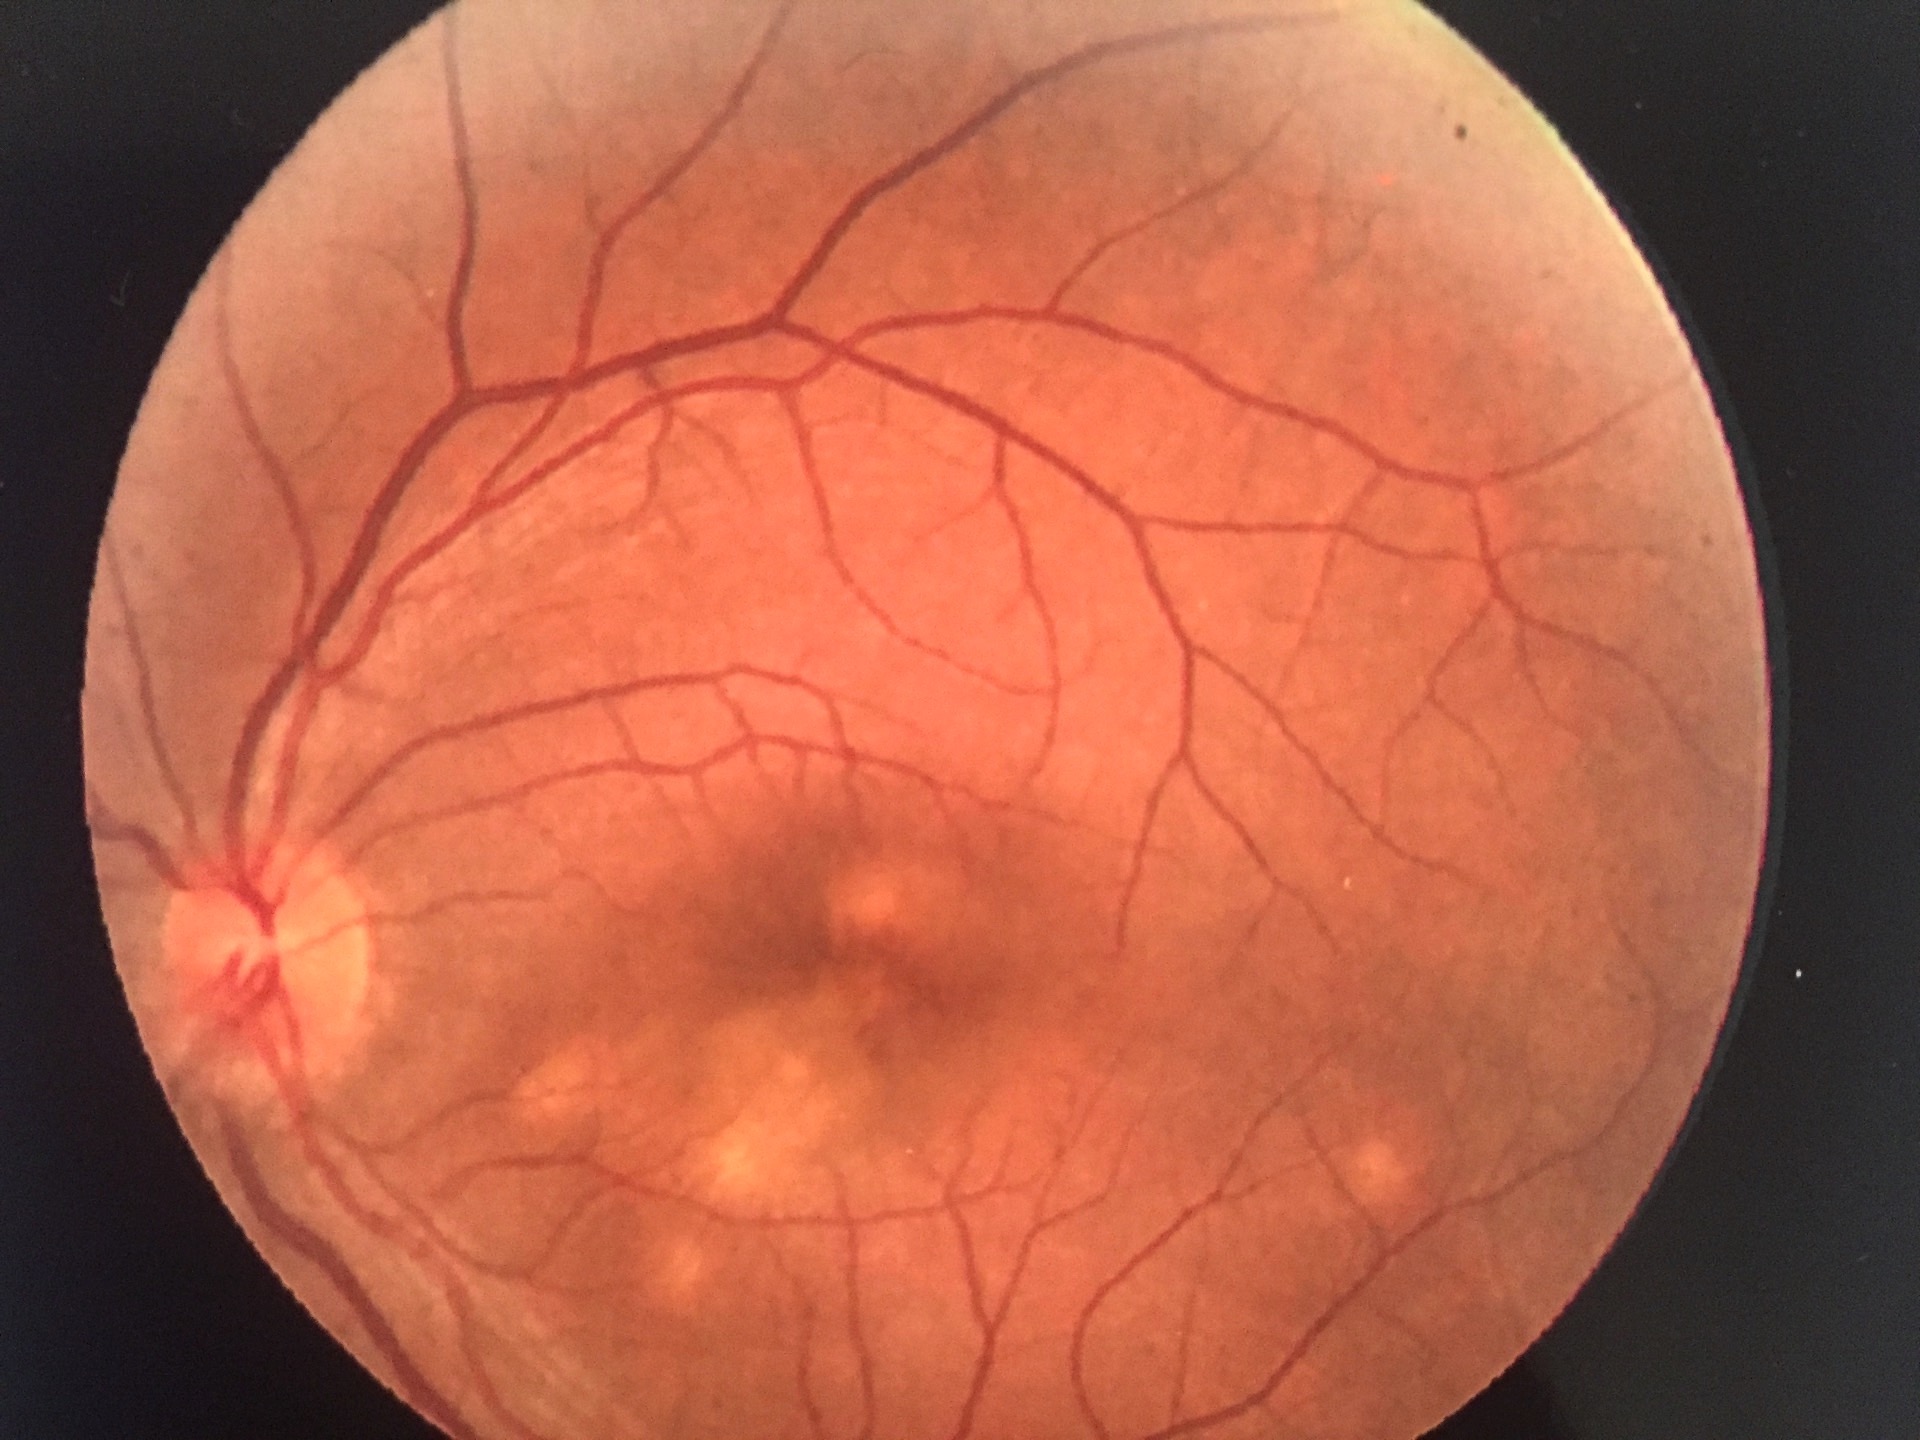

Fond d'oeil : corps flottants, myopie forte, trou/déchirure de rétine, myodesopsie

Pathologies rétiniennes : DMLA - dégénérescence maculaire liée à l'âge, diabète, myopie forte, occlusion veineuse...